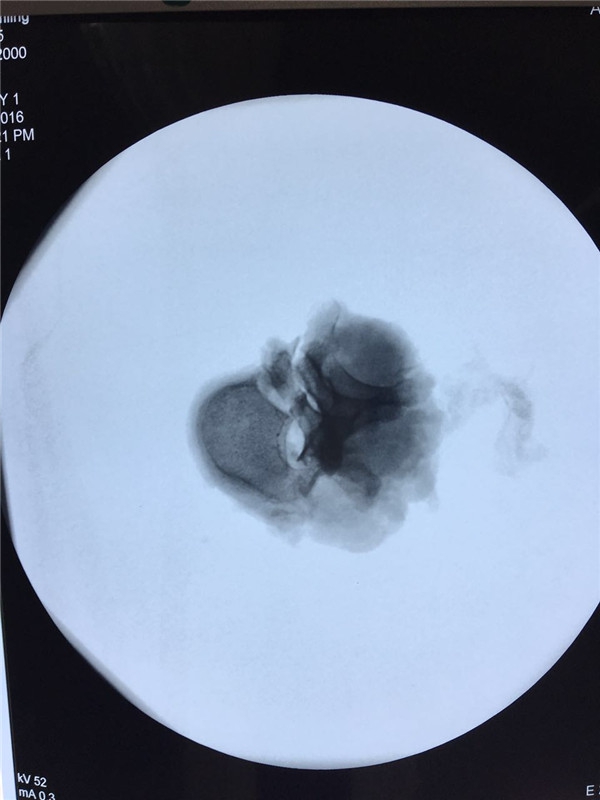

术中 椎体切除

术中透视